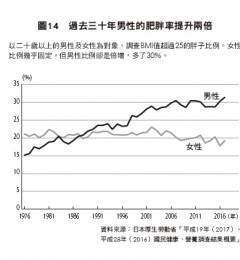

年龄段常见癌症情况

60岁以下男性中.肺癌是最常见和死亡率最高的癌症之一.其次是肝癌和胃癌.60岁~男性肺癌和胃癌高发。男性癌症病发和死亡例多出现在60~76人群.

30~56岁女性中.乳腺癌是最常见的癌症之一.60岁以上女性肺癌高发.乳腺癌是45岁以下女性常见癌症死因.其次是肺癌. 女性癌症病例高发于60~76岁人群.